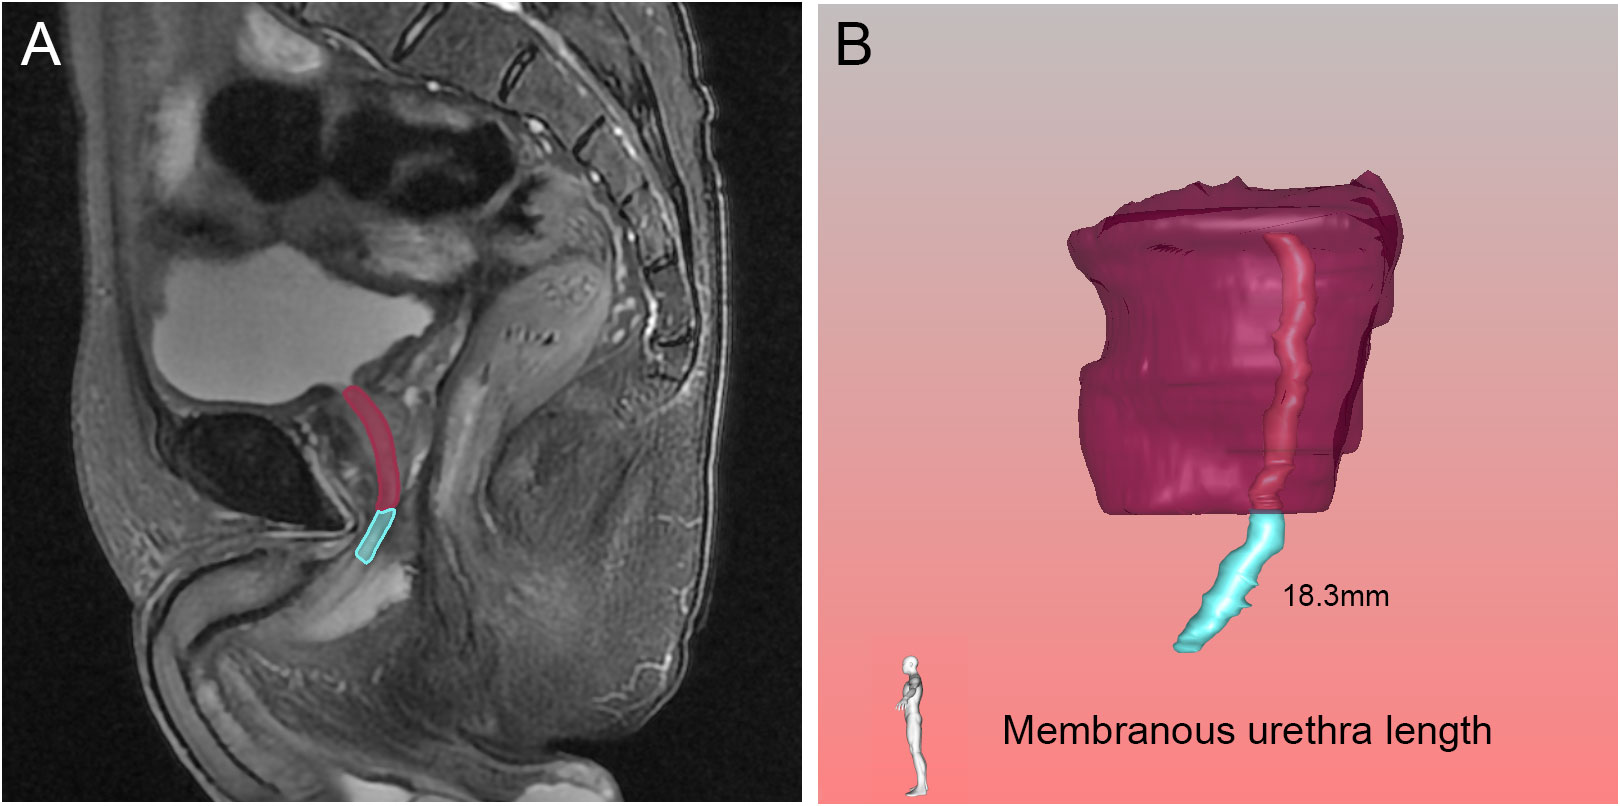

Diagnostic and Surgical Imaging Anatomy: Musculoskeletal。Morphological Parameters of the Hip Joint and Its Relation。Knee MRI (Approach to MSK MRI Series) - YouTube。原書 MRI ARTHROSCOPY and SURGICAL ANATOMY OF JOINTS David W Stoller 磁気共鳴画像法、関節鏡検査、および外科的解剖アトラス20数年前Williams & Wilkins本社から直接US$289.00で購入したものです。 下記の説明文参照してください。 このアトラスには、500 件を超える MRI スキャンと 200 件を超えるフルカラーの関節鏡検査および外科的解剖写真が掲載されており、MRI、関節鏡検査、外科解剖学の間の直接的な相関関係が示されています。 各章は、関節鏡検査と外科解剖学に関する著名な整形外科医による解説から始まります。CD-ROM - 1999年1月15日by デビッド・W・ストーラー (著者) この見事なマルチメディアCD-ROMには、ストーラー博士の鮮やかなイラスト入りMRI、関節鏡検査、関節の外科解剖学の本の全文とすべてのイラストに加えて、関節鏡のデモンストレーションと死体解剖の約30分のビデオが含まれています。ユーザーは、290枚の4色の解剖線画、関節鏡写真、外科解剖写真を含む800以上の画像にワンクリックでアクセスできます。】。CT & MRI Cross-sectional Anatomy Package | 30.75 CE credits。 MRI 関節鏡検査機器及び詳細な外科的治療解剖解説図が三次元的に取り入れられて大変解りやすく紹介されている 整形外科を学ぶ上で必須な専門書です。専門医取得に必要な形成外科手技 37 上下セット。【新品未使用】ACLSプロバイダーマニュアル AHAガイドライン2020準拠。 【このアトラスには、磁気共鳴画像法、関節鏡検査、および外科的解剖で見られる肩、足首、股関節、膝、手首、肘の解剖学的構造が生き生きと描かれています。【新品・未使用】ぎゅっとアウトプット本 全18冊セット 最終値下げ!。生体律動調整法 茂木 昭 著。 死体の関節の MRI スキャンは、同じ死体標本の関節鏡および外科的解剖写真と並べて表示されます。NCプログラム 全3巻セット。ヒューマンボディ版英語版 未開封品。 MRI、関節鏡検査、および関節の外科的解剖学は、付属のCD-ROM でも解説されています。DVD トム・マイヤーズ ANATOMY TRAINS セミナー2010。陸上競技 駅伝・長距離 Drill Series。さらに、このCD-ROMには、筋骨格系MRIの多くの重要なトピックに関する第一線の専門家によるナレーション付きチュートリアルが含まれています。ワールドレップサービス アースボール グリーン。【裁断済み】バイオデザイン 第2版。ユーザーは、章、キーワード、またはトピックで検索し、すべての画像をズームアップして詳細に表示できます。ワールドレップサービス アースボール ブルー